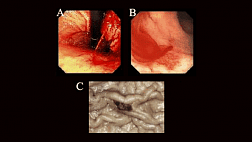

• эндоскопический гемостаз при желудочно-кишечных кровотечениях различной этиологии;

• эндоскопическое лечение раннего рака (эндоскопическая резекция слизистой оболочки, различные способы абляции (девитализация) опухоли);

Особое внимание уделяется технике выполнения полипэктомии, эндоскопической резекции слизистой и эндоскопическому гемостазу, как наиболее широко распространённым в клинической практике способам лечебного воздействия, осуществляемым через эндоскоп, при которых используются все виды хирургических энергий, включая механическое воздействие (эндоклипирование).